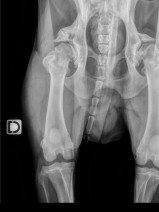

• Orthopédie

L’arthrose est la première affection articulaire rencontrée chez le chien. Cette formation a pour objectif de faire le point sur cette affection en abordant les moyens actuels d’évaluation et de suivi de l’animal arthrosique et la prise en charge multimodale du patient arthrosique.

Plusieurs présentations seront axées sur le dépistage précoce et la prise en charge des atteintes articula...